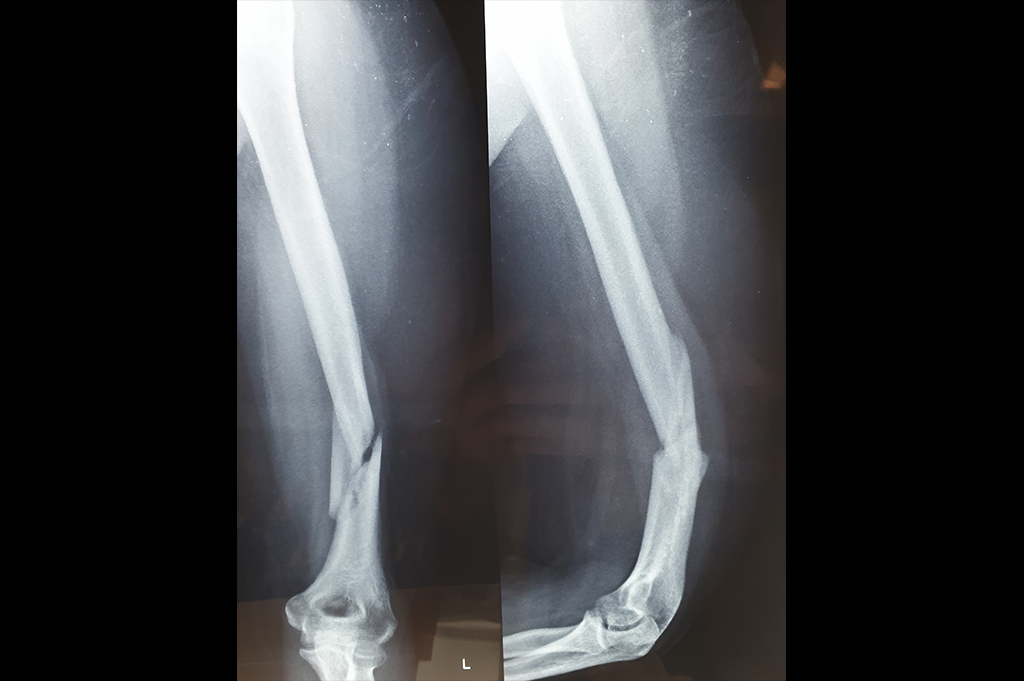

Elbow